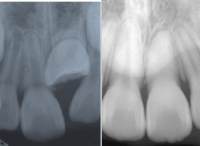

日本矯正歯科学会専門医課題症例(その他の症例2)

カテゴリー:埋伏歯牽引症例(代替症例)

埋伏歯を矯正歯科的に牽引することで、正常咬合を確立できた症例。

最良の解決策は、口腔外科的に開窓後、矯正歯科的に牽引し咬合に参加させることである。単に萌出させたと言うだけでなく、牽引後マルチブラケット装置を使用し、正常咬合を確立したケースの提示が求められている。